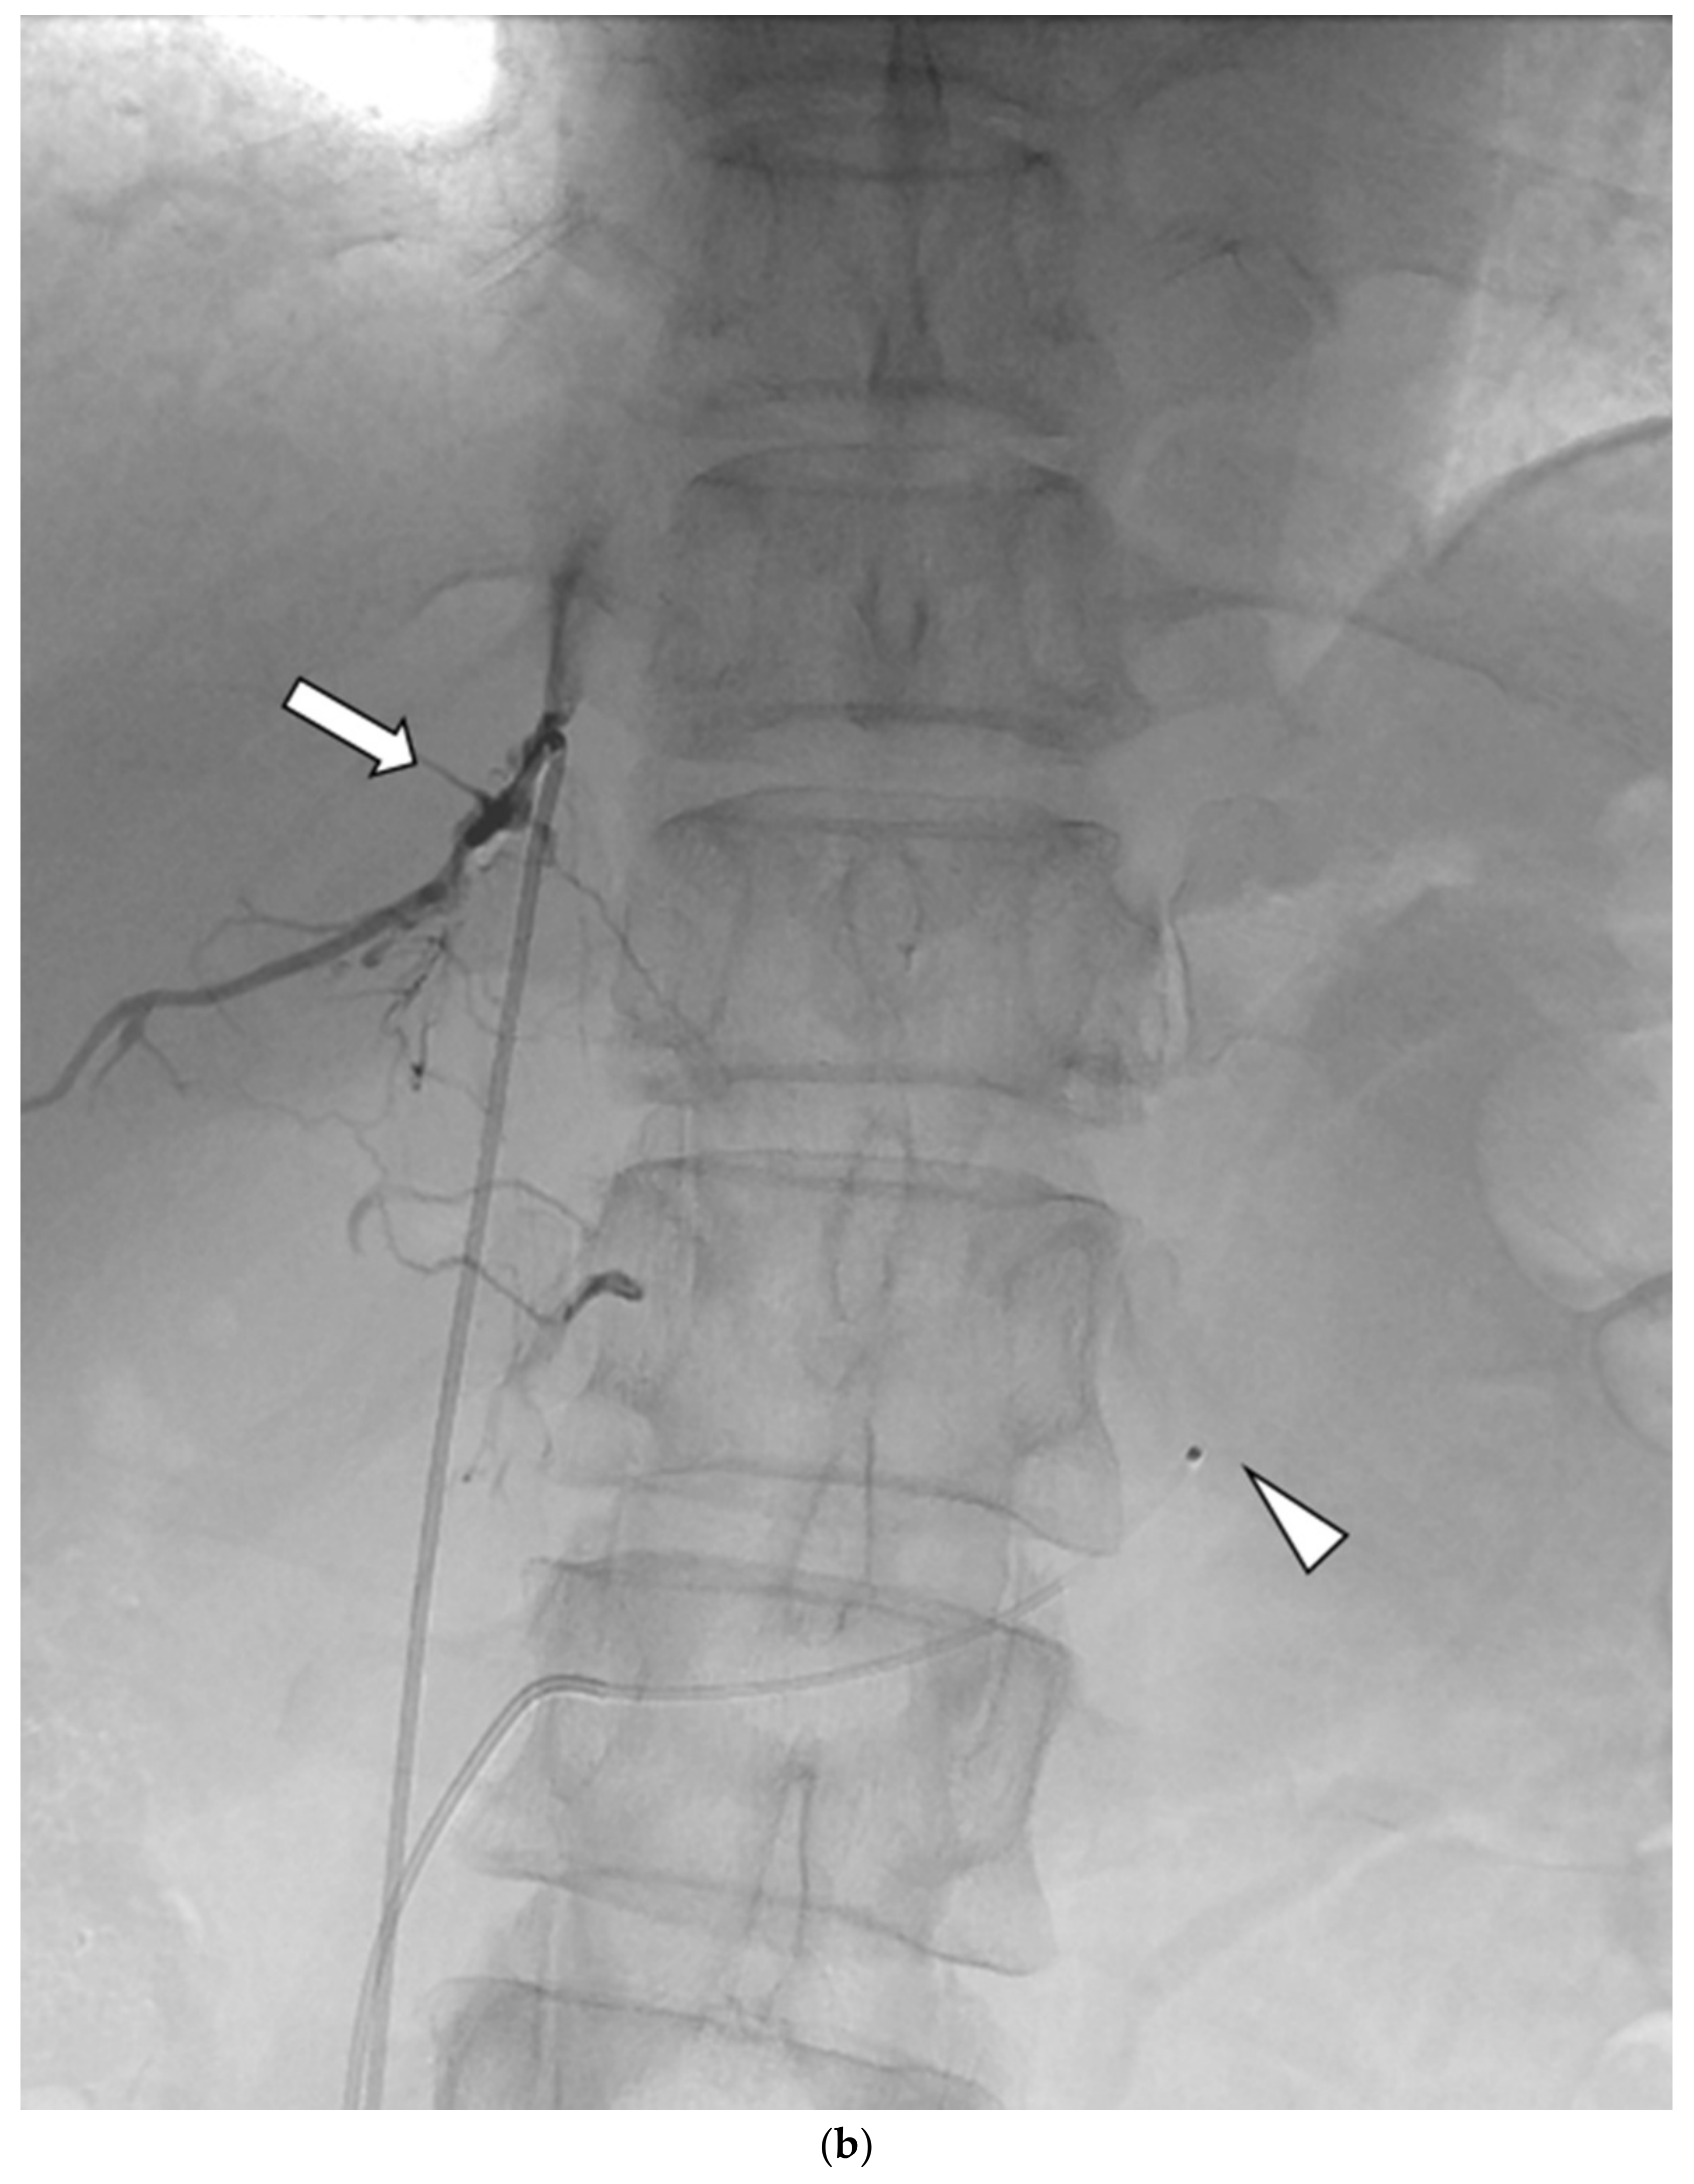

AVS was always conducted by 2 or 3 senior radiology residents or a radiologist with supervision by one of four interventional radiologists, after the administration of anticoagulant therapy with 3000 units of heparin. Under local anesthesia, 4-Fr sheaths were percutaneously inserted in the femoral veins of both legs. Before and after (between 15 and 30 min) bolus injection of 0.20 mg of the adrenocorticotropic hormone (ACTH) (cosyntropin), at least 3 mL of venous blood were sampled from the following four sites: the lowest point of the inferior vena cava (IVC) and the left AdV, the right AdV, and the IVC at one vertebral level above its confluence with the right AdV (the substitute right AdV [S-rt. AdV]). For the S-rt. AdV, the tip of the catheter was positioned on the same side of the IVC as the right AdV. Figure 1 shows how the positions of the S-rt. AdV were determined. For cannulation of the left AdV, a 4-Fr catheter of Simons-type (Terumo, Tokyo, Japan) and a 1.7-Fr microcatheter (Boston Scientific, Marlborough, MA, USA) were mainly used, and sampling from the main trunk of the left AdV was conducted via a 4-Fr sheath (Medikit, Tokyo, Japan) inserted into the left femoral vein. For cannulation of the right AdV, a 4-Fr Cobra-type (Medikit, Tokyo, Japan) or Hook-type (Medikit, Tokyo, Japan) catheter inserted into the right femoral vein via a 4-Fr sheath was used. The same microcatheter was used for the right AdV if blood could not be withdrawn from the 4-Fr catheter. Digital subtraction angiography (DSA) was performed using an Allura Xper FD20 (Philips Healthcare, Best, Netherland) and a Infinix 8000v (Canon Medical Systems, Tochigi, Japan). For patients in whom it was difficult to determine whether the catheter had entered the right AdV, an unenhanced or enhanced cone-beam CT was performed to confirm the locations of the catheters in the right AdV.

Figure 1.

Schematic diagram (a) and digital angiography (b,c) of the location of catheter placement in the S-rt. AdV. The catheter tip is placed at one vertebral level above the confluence of the IVC with the right AdV, and its orientation is adjusted so that it is pointing toward the right dorsal side in the same way as the right AdV.